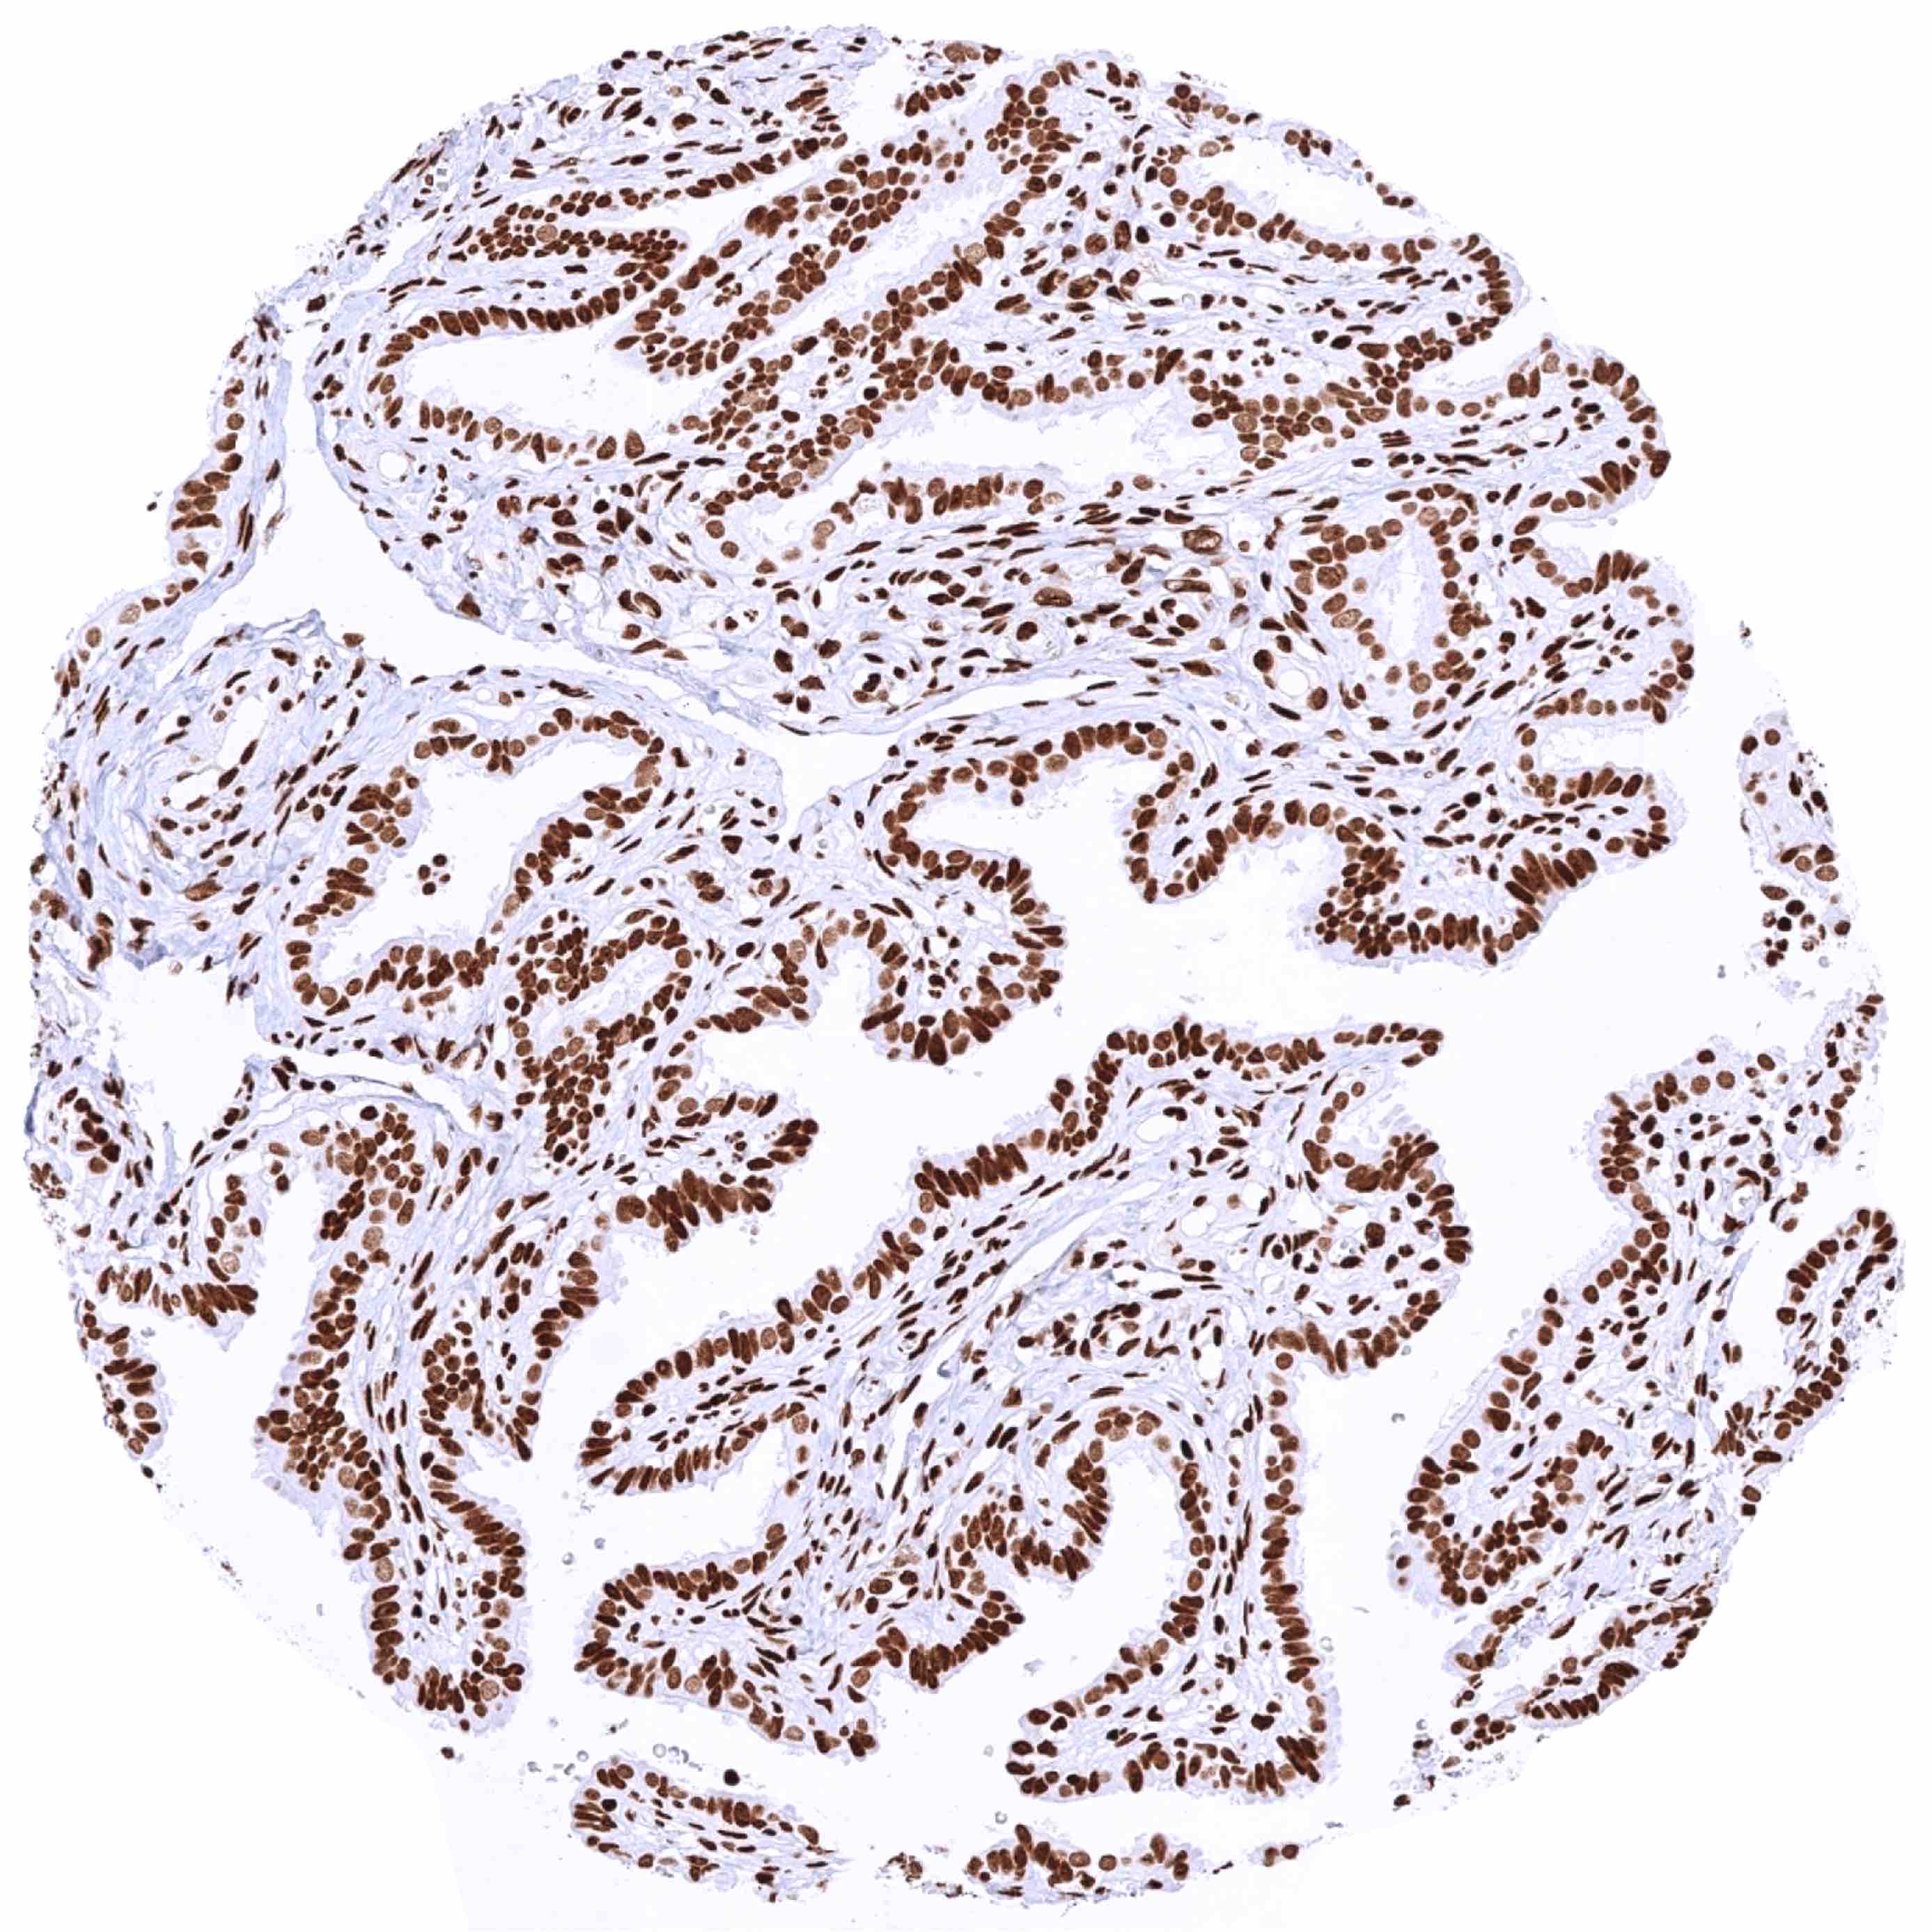

Uterus, endocervix